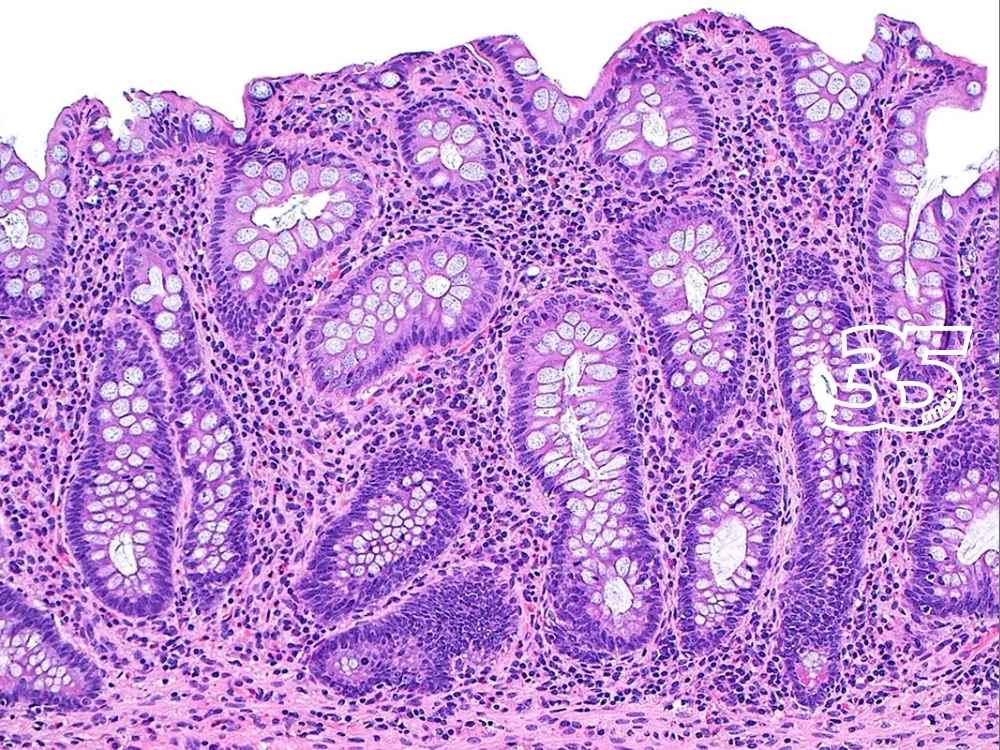

Divididas basicamente entre doença de Crohn (em todo o aparelho digestivo) e retocolite ulcerativa (no cólon, a porção final do intestino), as condições causam inflamação crônica do intestino e podem desencadear úlceras. Ainda não se sabe exatamente como as DIIs se desenvolvem, mas pesquisas sugerem que a flora intestinal pode desencadear uma reação imunológica em pacientes com predisposição genética.

“O objetivo é que, ao fazer uma biópsia, ultrassom ou endoscopia, não se encontre doença ativa. Não basta se sentir bem, é importante estar bem”, explica a diretora de assuntos médicos em imunologia para a América Latina Tatiana Deschamps, da Johnson & Johnson.